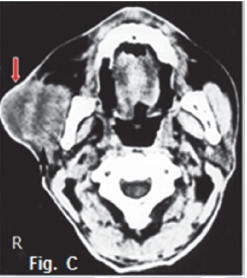

Fig. A is a photograph of a 65 year old male patient presenting with a slow growing swelling of the parotid gland on the right side of the face, which he noticed about eight months ago. Sialography of the parotid gland (Fig. B) shows that contrast medium uptake is prevented by tumour formation, resulting in a poorly imaged right parotid gland (arrow). Fig. C is an axial CT of the same patient demonstrating an ill-defined tumour with an infiltrative margin, indicating malignancy. The right masseter muscle also lacks definition because of infiltration by a malignant tumour (red arrow). A diagnosis of an epidermoid carcinoma was made. The tumour was termed mucoepidermoid by Stewart et al in 1945, who considered it to be divided into benign and malignant types. The WHO regards this tumour as a lesion with malignant potential but believes that, in a variety of clinical instances, it is inappropriate to call any of these tumours "carcinomas". The WHO consider this neoplasm to be intermediate between adenoma and carcinoma. Thirty percent of mucoepidermoid malignancies occur in the salivary glands and appear commonly in the 3rd to 4th decades. The sialogram in Fig. D shows irregular non filling defects suggestive of a malignant pleomorphic adenoma (malignant mixed tumour). The CT sialogram (Fig. E) of the same patient shows an ill-defined tumour mass (arrow). Pathologically, malignant pleomorphic adenoma results from the transformation of the epithelial tissue in a pleomorphic adenoma. These tumours occur predominantly in patients older than 50 years. The transverse T1 weighted MRI scan (Fig. F) of an adenocarcinoma of the right parotid gland shows a poorly defined, non-homogeneouus, infiltrating mass (arrow). Adenocarcinomas most commonly involve the minor salivary glands and submandibular glands, accounting for 5% to 10% of salivary gland tumours. A break in the duct and leakage of contrast medium are sialographic signs of malignancy, and are usually found in epidermoid carcinoma, adenocarcinoma, and high-grade mucoepidermoid carcinoma. However, most of the malignant tumours have a low rate of malignancy.